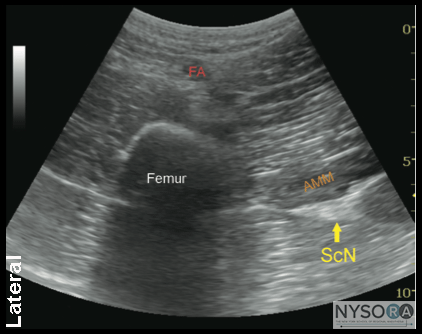

Figure 1-3: Ultrasound anatomy of the sciatic nerve. From superficial to deep; femoral artery (FA) and femur laterally, adductor magnus muscle (AMM) and sciatic nerve (ScN) laterally. The sciatic nerve is typically located at a depth of 6 to 8cm. General Considerations The anterior approach to sciatic block can be useful in patients who cannot be positioned in the lateral position due to pain, trauma, presence of external fixation devices interfering with positioning, and other issues. It also may be well-suited to patients who require postoperative blocks for analgesia following a total knee arthroplasty. Ultrasonography adds the benefit of no requirement for the palpation of a femoral pulse or the use of geometry for identification of the skin puncture point. In addition, using the ultrasound-guided approach should reduce the risk of puncture of the femoral artery as compared with the landmark-based approach. The actual scanning and needle insertion are performed on the anteromedial aspect of the proximal thigh, rather than the anterior surface, and may require a slight abduction and external rotation of the thigh. This block is not well suited to insertion of catheters because a large needle must traverse several muscles (causing pain and possibly hematomas), an awkward catheter location (medial thigh), and catheter insertion at approximately perpendicular angle to the sciatic nerve is difficult. Ultrasound Anatomy The sciatic nerve is imaged approximately at the level of the minor trochanter. At this location, a curved transducer placed over the anteromedial aspect of the thigh will reveal the musculature of all three fascial compartments of the thigh: anterior, medial, and posterior (Figures 1-2 and 1-3). Beneath the superficial sartorius muscle is the femoral artery, and deep and medial to this vessel is the profunda femoris artery. Both of these can be identified with color Doppler ultrasound for orientation. The femur is easily seen as a hyperechoic rim with the corresponding shadow beneath the vastus intermedius. Medial to the femur is the body of the adductor magnus muscle, separated by the fascial plane(s) of the hamstrings muscles. The sciatic nerve is visualized as a hyperechoic, slightly flattened oval structure sandwiched between these two muscle planes. The nerve is typically visualized at a depth of 6 to 8 cm (Figure 1-3). ![]() Figure 1-4: Transducer position to visualize the sciatic nerve through the anterior approach. Distribution of Blockade Sciatic nerve block results in anesthesia of the posterior aspect of the knee, hamstrings muscles, and entire lower limb below the knee, both motor and sensory, with the exception of skin on the medial leg and foot (saphenous nerve). The skin of the posterior aspect of the thigh is supplied by the posterior cutaneous nerve of the thigh, which has its origin from the sciatic nerve more proximal than the anterior approach. It is, therefore, not blocked by the anterior approach. Practically, however, the lack of anesthesia in its distribution is of little clinical consequence. Equipment Equipment needed is as follows: